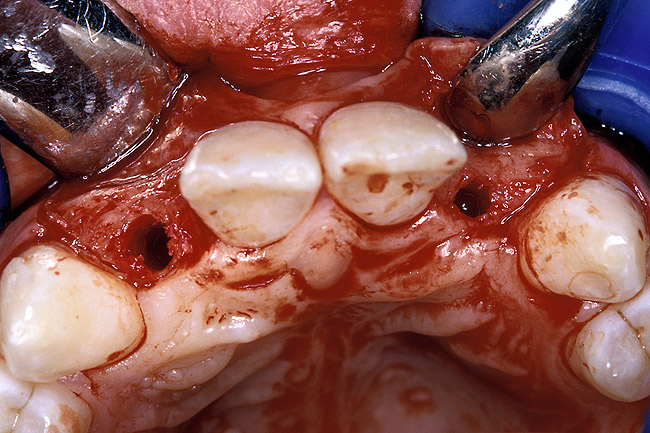

Periapical radiographs were taken to help determine the mesial-distal inclinations of the adjacent tooth roots (Figure 1). The radiographs revealed a serious issue, convergent roots for the right canine and right central, which eliminated that area as a potential implant-receptor site. The space between the left central and canine teeth was minimal, although the roots were relatively parallel. Clinical examination (manual palpation of the root eminences superiorly to the vestibule on the right side) confirmed the root convergence (Figure 2A). The flat, wide zone of the keratinized tissue and lack of interdental papilla was evident for the missing right lateral incisor. There was a marked difference in clinical appearance for the left lateral, which could impact the eventual plan of treatment (Figure 2B). Other significant clinical findings included bilateral facial bone concavities, which existed as a result of the congenitally missing tooth roots. As a diagnostic cue to the underlying bone topography, it is important to follow the demarcation between attached and unattached gingival tissue, and note the crestal width of the available keratinized tissue (Figure 2C).

Before the day of surgery, the patient was seen by the orthodontist for the removal of the orthodontic brackets. The patient still was not pleased with the position of the two centrals, and it was determined that this would be addressed after implant placement (Figure 13A). The anatomical variations of the crestal tissue and lack of interdental papilla can be appreciated in the close-up views of the right and left sites (Figure 13B and 13C). There were no surprises on the day of surgery as all of the decisions were made during the planning phase, before the scalpel ever touched the patient. The occlusal view of the CT 3D model revealed the wider alveolar ridge on the right side and thinner crest on the left side (Figure 14A). This was confirmed when the full thickness mucoperiosteal flaps were elevated, and the underyling bone revealed (Figure 14B). The tooth-borne templates were designed to facilitate the drills and drilling sequence specific to the diameters of the predetermined implants (Figure 15A). Each template contained an embedded 5-mm long stainless steel tube, which was approximately 0.2-mm wider than each drill (just wide enough to allow for the drills to rotate freely). Once positioned over the natural teeth, the template was secure and offered precision accuracy in transferring the implant locations from the original software-designed plan, allowing the potential for internal and external irrigation (Figure 15B). The 3.7-mm diameter Tapered Screw-Vent implant drilling sequence requires three drills: pilot, intermediate, and final sizing. Thus, three separate templates were fabricated to a.commodate these sizes. The templates were removed easily and replaced with the next sequential size in less time than it takes to change the drill on the surgical handpiece. After the osteotomies had been.completed, the implants were delivered to the site (Figure 16A and Figure 16B). For this internal hex connection implant, the author r.commends that the flat of the antirotational hex be positioned to the facial for proper orientation of the restorative.components (Figure 17A). Preprepared margins were created from a milled titanium fixture mount transfer post, which was delivered to the implant as support for an immediate transitional restoration. The facial “dot” helped confirm the orientation of the abutment to the facially positioned flat side of the internal hex connection (Figure 17B). Before cementation of the transitional acrylic restorations, a closed-tray, fixture-level impression was made, and a soft-tissue model fabricated.

Figure 2a  Pretreatment buccal views showed (A) root convergence, (B) a difference in clinical appearance of the left lateral, and (C) significant crestal width of keratinized tissue.

Figure 2a

Figure 2b  Pretreatment buccal views showed (A) root convergence, (B) a difference in clinical appearance of the left lateral, and (C) significant crestal width of keratinized tissue.

Figure 2b

Figure 2c  Pretreatment buccal views showed (A) root convergence, (B) a difference in clinical appearance of the left lateral, and (C) significant crestal width of keratinized tissue.

Figure 2c